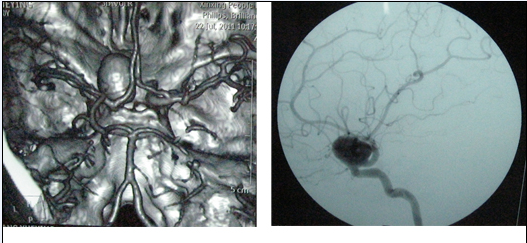

40岁的杨女士,因持续性头部胀痛2月余,加重伴恶心呕吐6小时,于近日急诊入院。入院CTA及全脑血管造影术显示:左侧颈眼动脉巨大动脉瘤,呈囊状,约52.5px*45px大小,瘤颈1.1175px。

术前检查结果